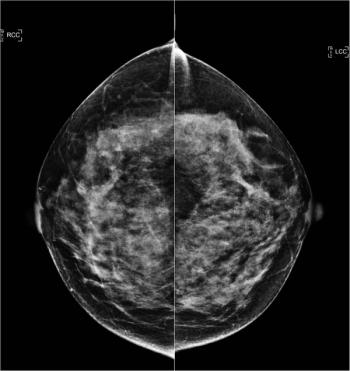

49-year-old patient presented for bilateral screening mammogram as well as bilateral screening ultrasound due to dense breast tissue.